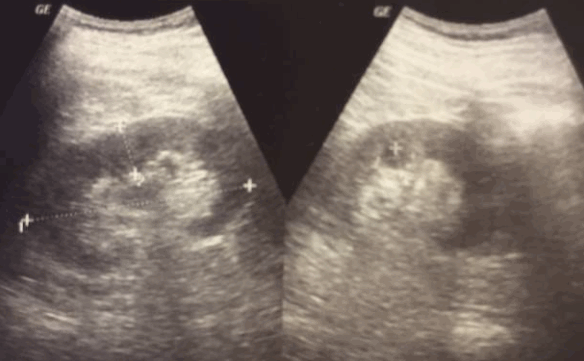

Односторонняя трансформация формы и повышение величины почки - наиболее частый симптом опухоли почки. Степень выраженности данного симптома находится в прямой зависимости от размеров опухоли и поверхностности ее расположения в паренхиме почки. Локализованное повышение размеров почки свойственно главным образом экстраренальным образованиям.

Яркость ультразвукового сигнала (эхогенность) от опухолей почек разнообразная: от анэхогенного сигнала до гиперэхогенного. Основная часть опухолей почек характеризуются сигналом, равным по интенсивности паренхиме почки (изоинтенсивный). В меньшей степени на УЗИ почек образование будет более гипоэхогенным, чем сама почечная паренхима.

По мере роста опухоли почки на УЗИ чаще имеются симптомы некротических изменений новообразования. Выраженность последних вместе с ультразвуковыми признаками обызвествления в ткани опухоли определяет эхоструктуру выявленных очагов. Как правило, опухоли почек имеют эхоструктуру, которая носит в главным образом разнородный характер различной выраженности, умеренной эхогенности и в большинстве случаев, обнаруживается без каких-либо проблем.